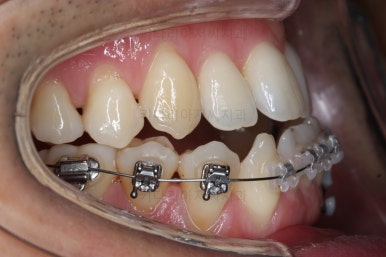

장치를 처음 부착했을 때의 입안 모습입니다.

아랫니가 해야될 작업이 많고 기간이 오래 걸리기 때문에 윗니는 최대한 늦게 장치를 부착하여 불편감을 최소화 하기로 했어요.

이번에 사용한 장치는 자가결찰 세라믹장치입니다. Empower clear(엠파워 클리어)라는 장치이고 흔히 많이들 알고계신 클리피씨와 동일한 유형의 장치에요.

클리피씨, 엠파워 등은 제품 이름일 뿐이죠. 클리피씨는 일본회사 장치, 엠파워는 미국회사 장치에요. 부산비수술교정 키다리아저씨치관느 여러 가지 이유로 엠파워 장치를 클리피씨보다 더 선호해요.